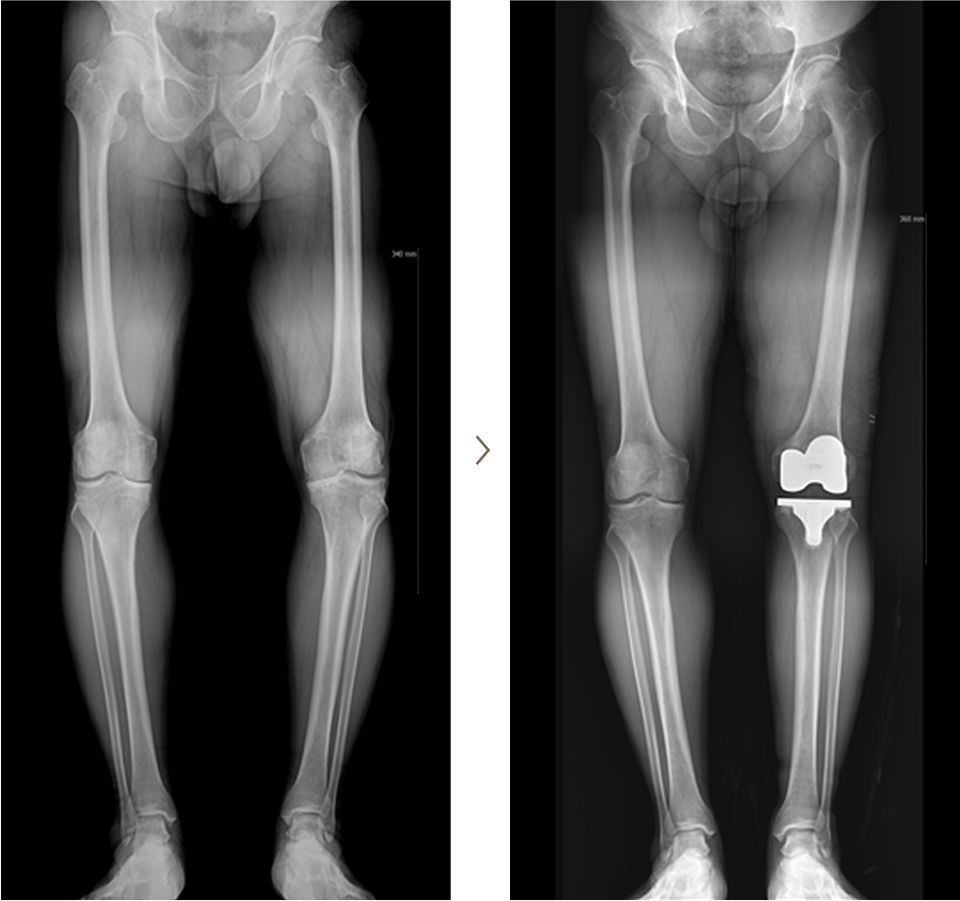

퇴행성 관절염 3-4기가 도달하면 인공관절 부분 치환술 또는 전체 인공관절 수술을 시행하게 된다.

인공관절 전체 치환술사례

- 환자 동의하에 게시된 이미지입니다.

인공관절 반치환술(부분 치환술) 사례

<수술전 엑스레이 사진>

<수술후 엑스레이 사진>